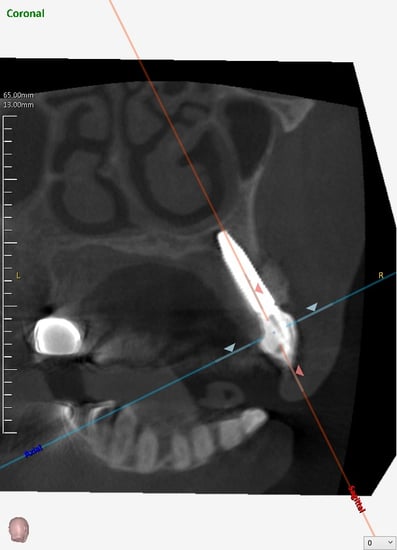

既存の骨の形態分類(ClassⅠ〜Ⅳ)のClassⅢまでは埋入可能とされています。

抜歯した直後にインプラントを埋入し、仮の歯を作製、唇側の骨のボリュームを保つために人工骨と結合組織を同時に移植する非常に優れた方法です。